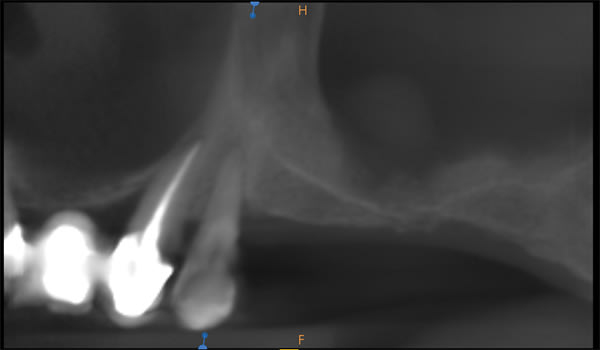

Severe Crestal Atrophy

The patient presented with the posterior mandible showing severe atrophy (Figure 16). The computed tomography (CT) scan showed 3.6 mm and 4.6 mm of available bone height with a failing premolar (Figure 17 and Figure 18). To regain function, the premolar was removed, and two Ultra-Short implants were placed in the molar region and splinted together (Figure 19 through Figure 22).